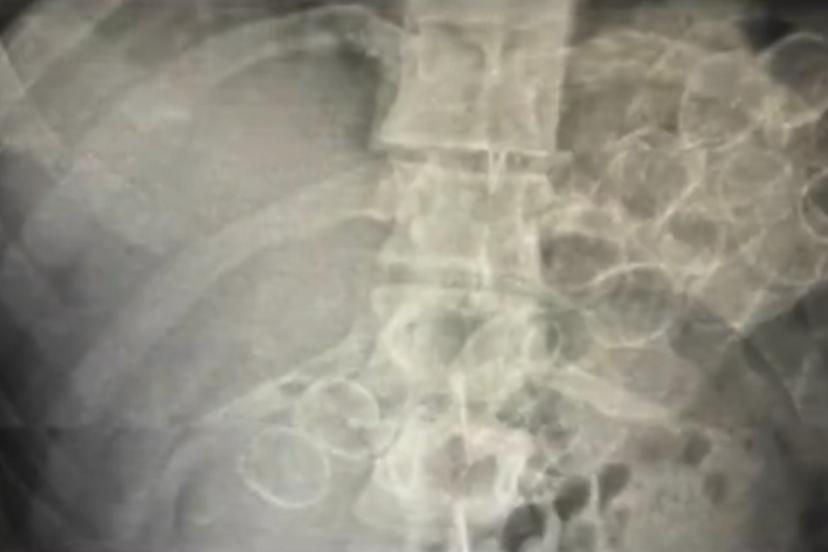

Bingöl’de polis ekiplerinin yaptığı çalışmada mide ve bağırsaklarında 75 kapsül halinde 775 gram metamfetamin maddesi ele geçirilen 3 şüpheli tutuklandı.

Bingöl İl Emniyet Müdürlüğü Narkotik Suçlarla Mücadele Şube Müdürlüğü ekiplerince yürütülen çalışmalar neticesinde, "Uyuşturucu veya Uyarıcı Madde Ticareti" suçu kapsamında 3 şahsın "yutma ve tıkma" yöntemiyle mide ve bağırsaklarında yüklü miktarda uyuşturucu madde taşıyarak kente getirdiği belirlendi. Ekipler tarafından yakalanan şüphelilerin hastanede yapılan tedavileri sonucunda, toplam 75 kapsül halinde 775 gram metamfetamin maddesi ele geçirildi.